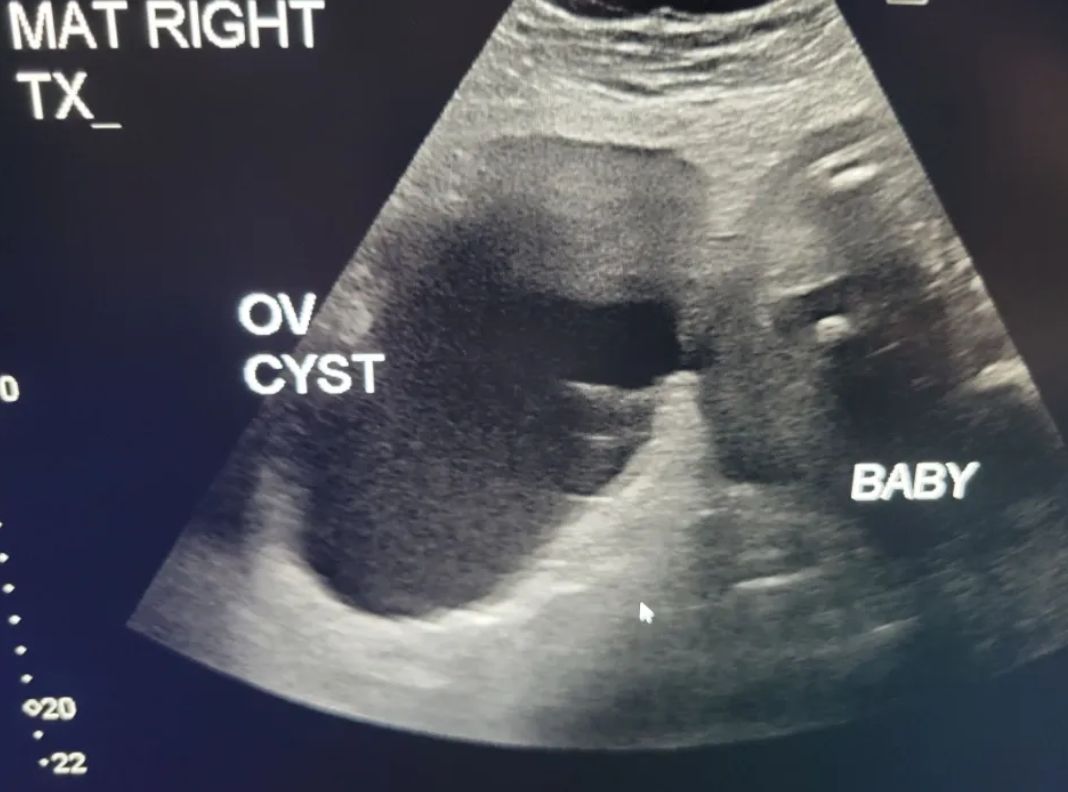

Torbiel jajnika była dwa razy większa niż płódTorbiel jajnika była dwa razy większa niż płód

- Pierwsze USG zrobiłam w siódmym tygodniu ciąży i wykazało dziewięciocentymetrową torbiel na prawym jajniku - mówi. - Lekarze nie zalecili operacji, ale powiedzieli, że jeśli zacznę odczuwać ból, to powinnam wrócić - dodaje.

- Tej nocy upadłam, a każdy najmniejszy ruch sprawiał tak ostry, przeszywający ból, że pojechaliśmy do szpitala - mówi. - Wyjaśniłam, że mam torbiel po prawej stronie, w miejscu bólu, więc wysłali mnie na USG. Okazało się, że ma już 17 centymetrów i w ciągu tygodnia urosła ponad pięć. Była wielkości melona - dodaje.

Torbiel ważyła już 1,8 kg, z kolei dziecko połowę tej masy. Mama została przewieziona do Montefiore St. Luke's Cornwall Hospital w Newburgh, gdzie przeszła szereg badań, by sprawdzić, czy guz nie jest nowotworowy. Szczęśliwie badanie MRI wykazało, że torbiel jest jedynie wypełniona krwią i płynem.